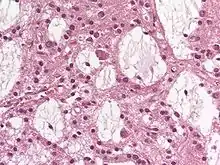

Dysembryoplastic neuroepithelial tumours are largely glioneuronal tumours, meaning they are composed of both glial cells and neurons.[2]

Three subunits of DNTs have been commonly identified:[2]

• Simple: Specific glioneuronal elements are the sole components of simple DNTs.[2]

• Complex: Glial nodules and/or type 3b focal cortical dysplasia (FCD), in addition to the glioneuronal elements are present in complex DNTs.[4] Both the nodules and FCD can be present within the same tumour, though only 47% of complex DNTs are linked to FCD.[2]

• Nonspecific: Nonspecific DNTs are lacking the glioneuronal elements common to DNTs but will show glial nodules and/or type 3b FCD.[2] Eighty-five percent of nonspecific case of DNTs show this FCD.[2]

There currently exists some debate over where to make the proper division for the subunits of DNTs. A fourth subunit is sometimes noted as a mixed subunit. This mixed subunit expresses the glial nodules and components of ganglioglioma.[1] Other findings suggest that DNTs require a reclassification to associate them with oligodendrogliomas, tumours that arise from solely glial cells.[3] These reports suggest that the neurons found within DNTs are much rarer than previously reported. For the neurons that are seen in the tumours, it is suggested that they had been trapped within the tumor upon formation, and are not a part of the tumour itself.[3]